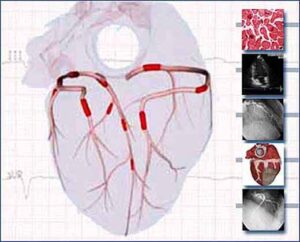

Eventi coronarici acuti: conoscere il grado di calcificazione delle placche nelle arterie

Il grado di calcificazione delle placche nelle arterie del cuore può utilimente essere integrato tra i fattori di rischio più...